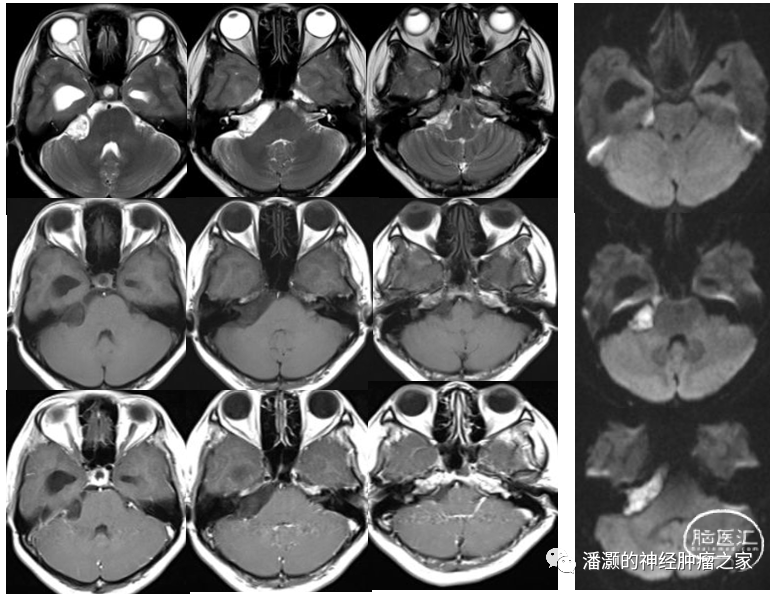

右侧CP角占位T2高信号、T1低信号,无强化,弥散成高信号,诊断考虑胆脂瘤。

脑室内占位呈混杂信号,与丘脑、透明隔关系密切,强化明显,内有混杂信号。强化可见大脑内静脉位于肿瘤下方。结合影像特征,考虑中枢神经细胞瘤。